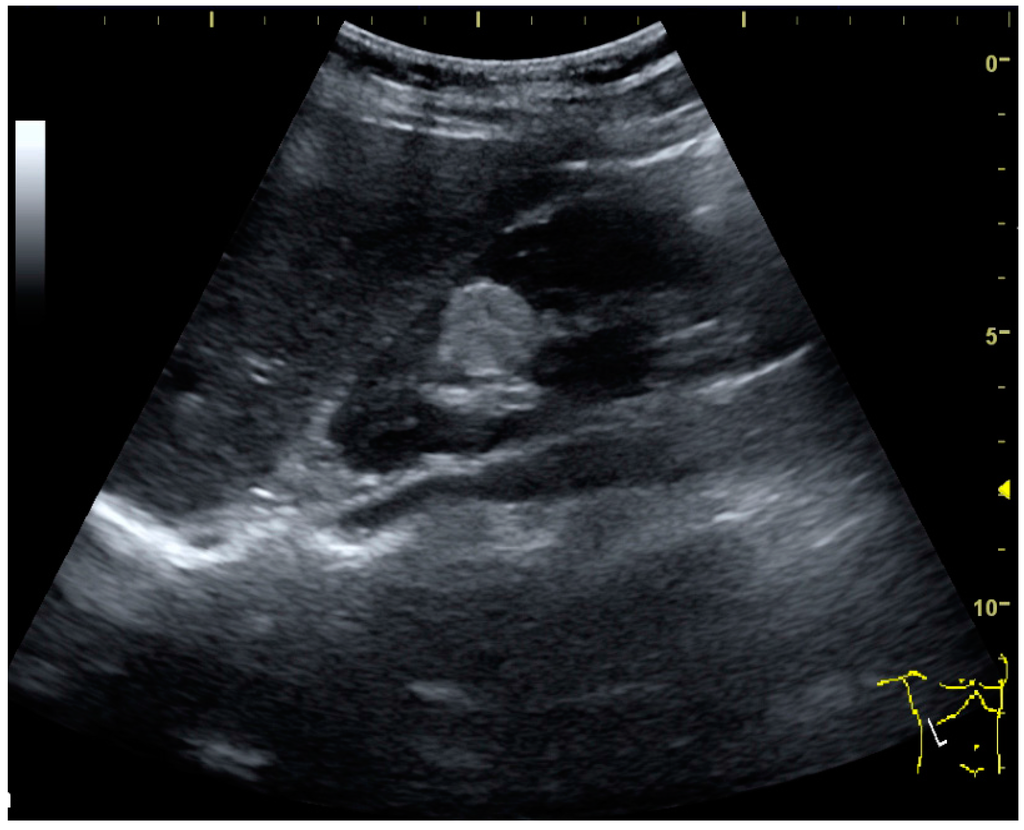

Other malignant tumors in the kidney are transitional cell carcinoma and squamous cell carcinoma, which arise from the urothelium and are found the renal sinus, as well as adenocarcinoma, lymphoma and metastases, which can be found anywhere in the kidney (Figure 10) [2,4].

Figure 10. Solid tumor in the renal sinus seen as a hypoechoic mass, later found to be lymphoma. The ‘1’ and ‘2’ on the US image are reference points used for CT fusion (not shown).